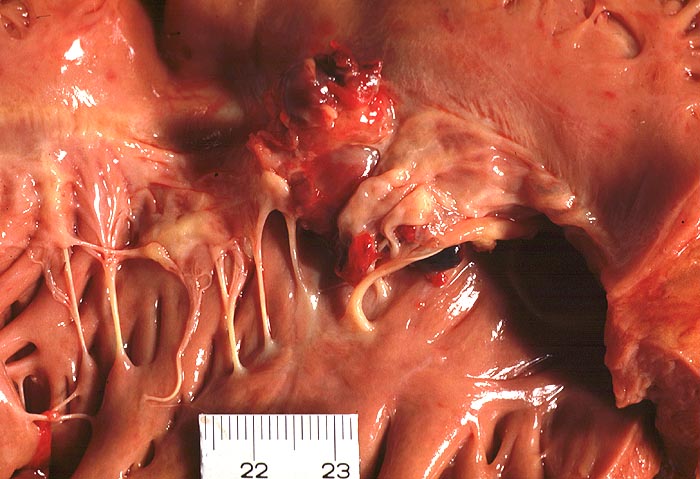

PathoPic ID 1382 - Ulzeropolypöse Endokarditis

Ulzeropolypöse Endokarditis

Trikuspidalklappe

Partiell destruierte Klappensegel mit polypoiden Vegetationen.

Nachweis von Staphylokokken in der Blutkultur.

Patient verstirbt wenige Stunden nachdem er komatös in seiner Wohnung aufgefunden worden war.